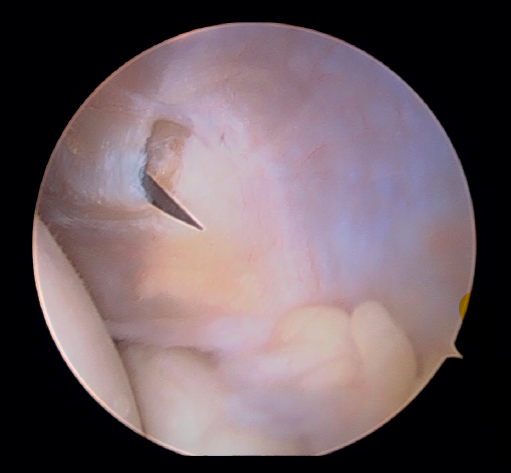

Posteriormente, se realiza la capsulotomía parcial lateral con sinoviotomo o vaporizador, hasta conseguir apreciar el ECRB (Figura 7). Una vez que se consigue su visualización, mediante el sinoviotomo y el vaporizador, se procede a la tenotomía de la inserción del ECRB en el epicóndilo, así como del tejido degenerativo tendinoso asociado (Figura 8). La liberación del tendón del ECRB debe limitarse a una zona anterior al eje central de la cabeza radial con el codo a 90°, para preservar la integridad del ligamento colateral lateral.

Figura 7. Tendón extensor carpi radialis brevis tras capsulotomía lateral (paciente en decúbito lateral, codo derecho, visión desde el portal medial).

Figura 8. Tenotomía del extensor carpi radialis brevis con vaporizador (paciente en decúbito lateral, codo derecho, visión desde el portal medial).